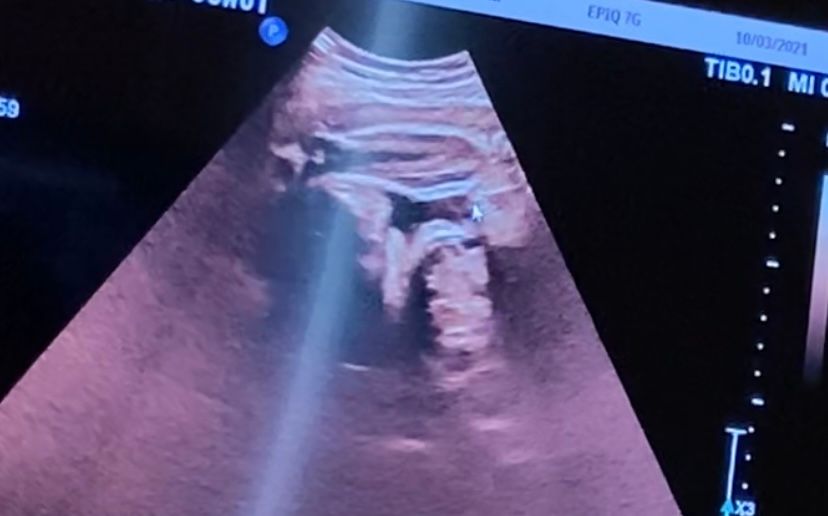

33 недели, кто рожал девочку а оказалось мальчика😅

УЗИ, КТГ, доплерСегодня был осмотр,узи ,ктг. Все супер, высокая(,вроде девочка)47 см. Вес средний -2230. Шейка почти 50 мм 😰я думала уже покороче.

а вот пол , у моего врача с самого начала под вопросом, вроде и девочка ,но она почему то не уверена. Постоянно сжатые ноги. Мне конечно уже все равно, я уже и хочу девочку и готово все для неё ,но вот эта неуверенность немного мучает. Вот только такие фото,но ничего здесь не видно, да?

А это не пипирка у нас?